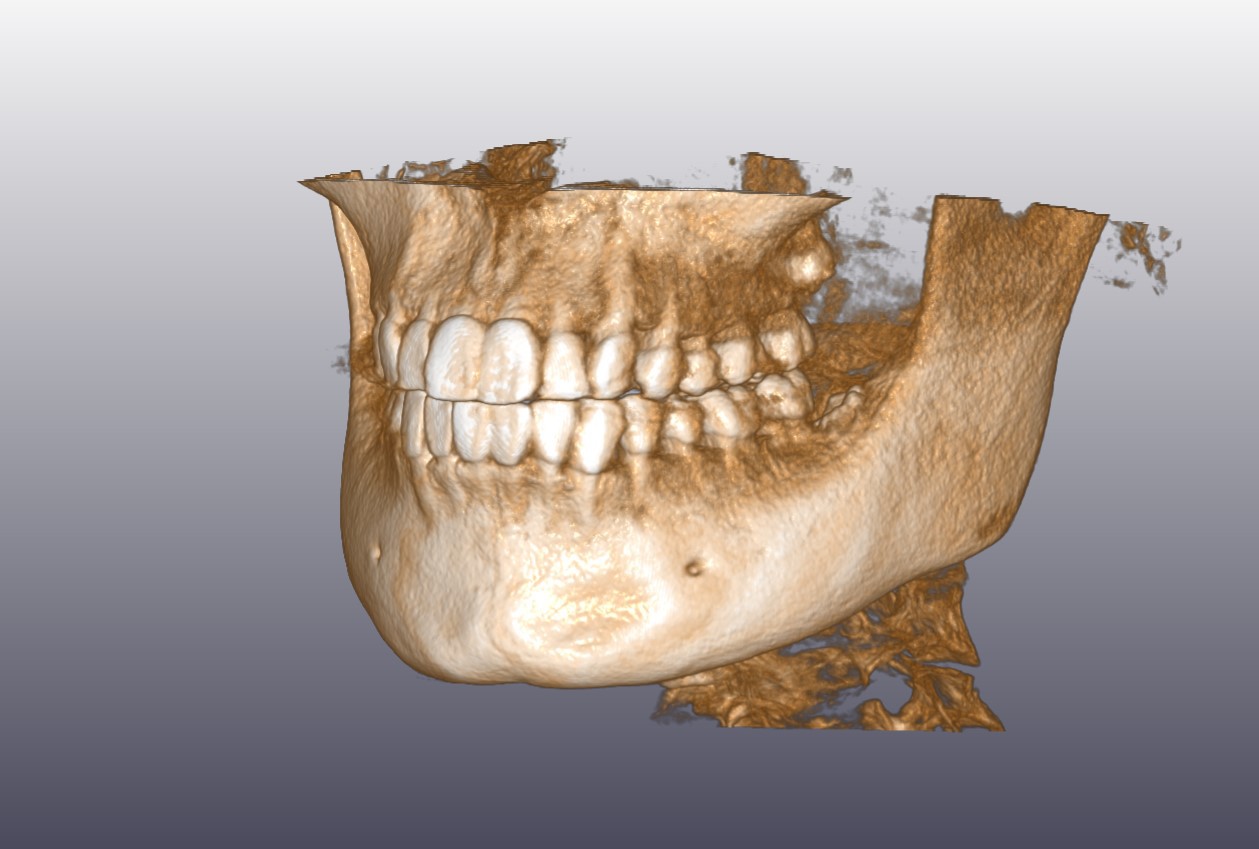

顎骨CT

顎骨CT(3D)